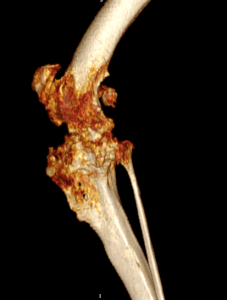

Total joint replacement of any joint carries the risks of possible complications. Therefore, total knee replacement is reserved for dogs with painful knee conditions, where either conventional surgical techniques have not been successful or where diseased joints are unresponsive to conservative management using pain relief and rehabilitation. The most common cause of knee pain is osteoarthritis secondary to cruciate disease, trauma or malformation of the knee. Examples of severe osteoarthritis are shown below:

Lucy is a 10-year-old golden retriever who was referred with significant pain and lameness affecting her left hind limb, attributed to considerable arthrosis of the knee. A CT scan revealed collapse of the medial compartment (one half of the knee) with bone-on-bone wear and complete erosion of the caudo-medial tibial plateau (parts of the tibia articular surface). In Lucy’s case, the cruciate and collateral ligaments were disrupted. Therefore, a custom rotating-hinge total knee replacement was designed and manufactured for her. The two components had one metal stem each that were anchored into the femur and tibia using cement, while hydroxyapatite cover on metal surfaces that had direct contact with bone helped with bone on-growth.